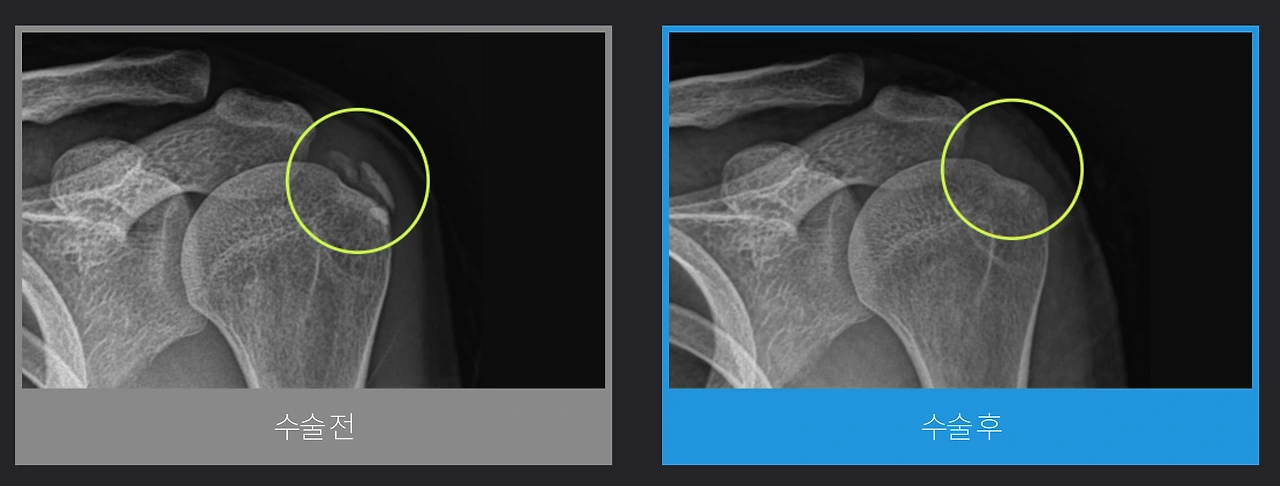

만일 초기지만 오랜 시간에 걸쳐 진행한 후에 발생하는 질환의 특징으로 통증이 심하거나 비수술적치료로도 개선이 되지 않는다면 관절내시경을 이용해 석회를 제거하는 수술을 할 수 있는데요. 통증의 원인을 빠르고 정확하게 제거하며, 최소절개로 인해 수술 후 회복시간이 짧은 장점이 있습니다.

어깨석회관절내시경.PNG